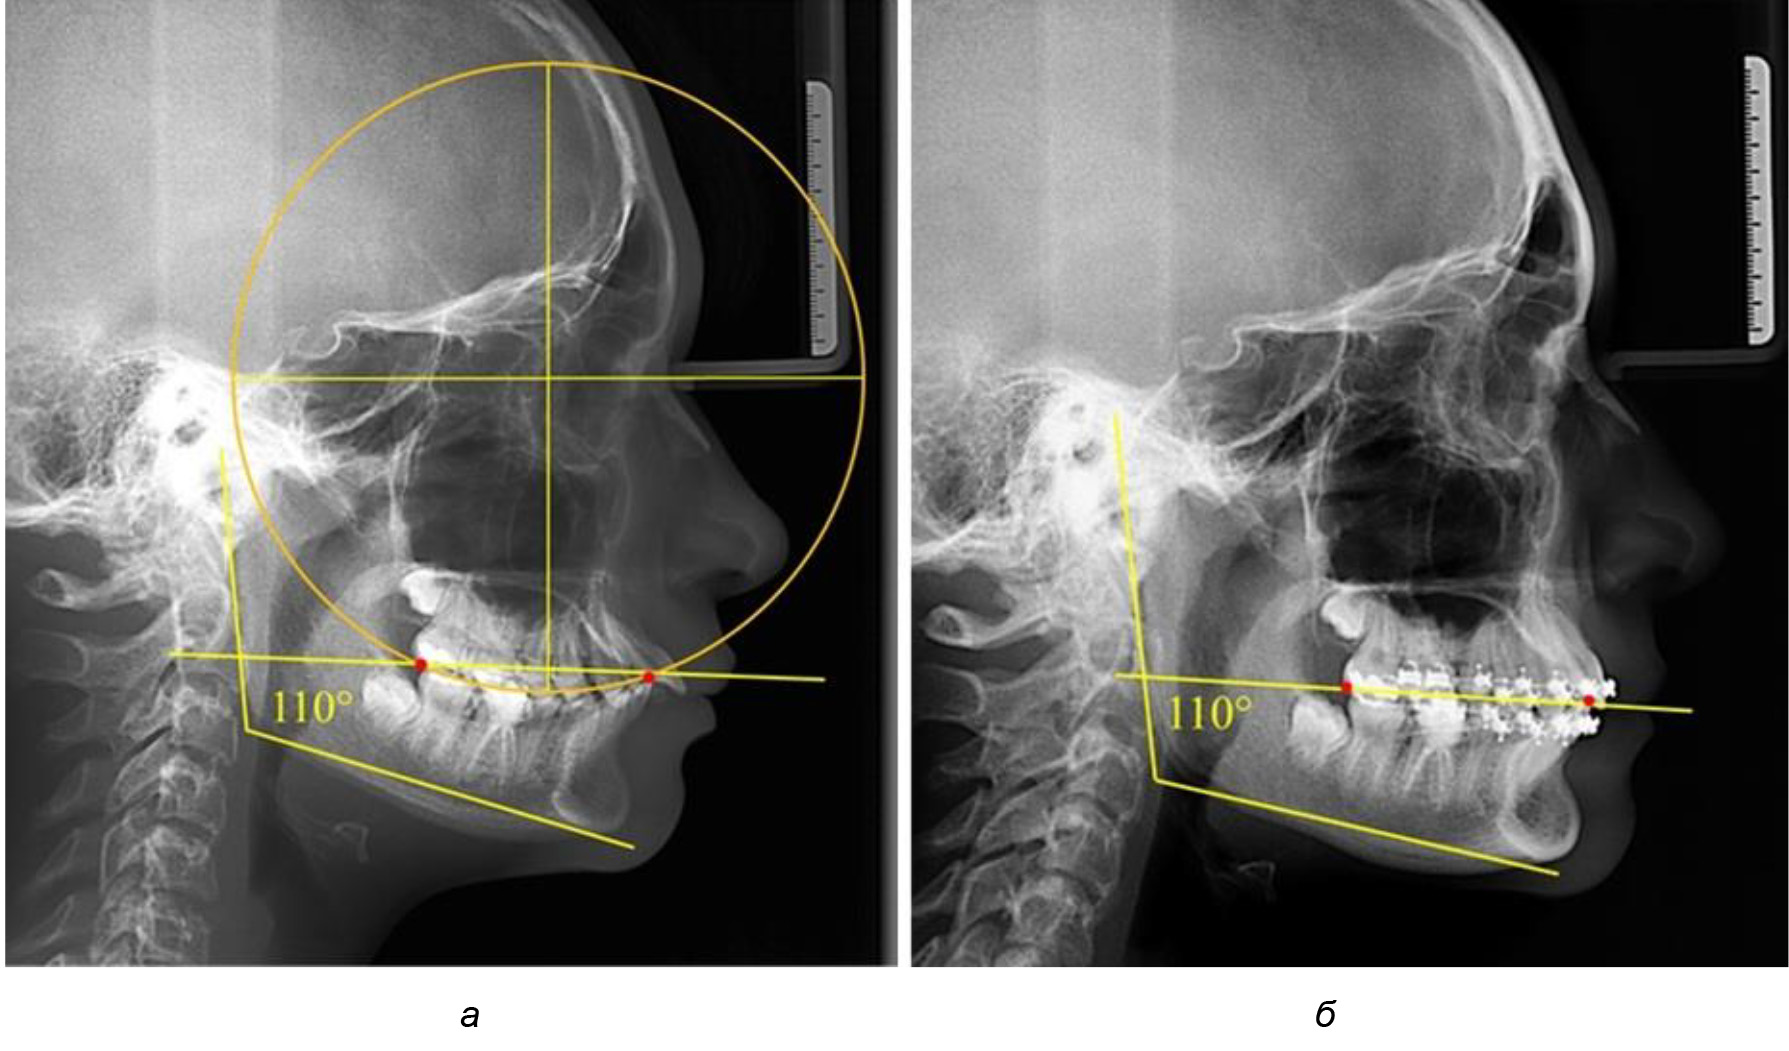

В ходе исследования установлено, что в 1-й подгруппу вошли ТРГ и ОПТГ 18 человек 1-й группы, что составило (29,03 ± 5,78) % от всех пациентов, рентгенограммы которых были проанализированы. У всех пациентов величина угла нижней челюсти была более 125° и в среднем составила (129,89 ± 3,62)° и характеризовала вертикальный тип нижней челюсти.

Деление величины радиуса круга к длине окклюзионной линии составило 1,623 ± 0,02. Таким образом, для определения радиуса окружности, соответствующей кривизне окклюзионного контура боковой ТРГ, необходимо измерить расстояние между передней и задней окклюзионными точками и последующим умножением полученной величины на число Фибоначчи (рис. 2).

Рис. 2. Особенности кривой Spee на ТРГ (а) и ОПТГ (б) у людей с признаками вертикального роста